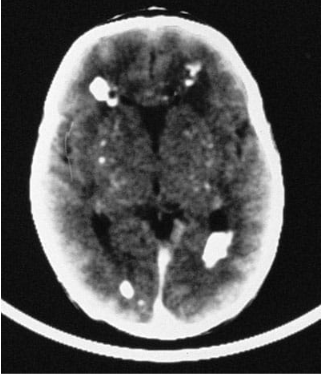

Lesões periventriculares

• Calcificações periventriculares (na toxoplasmose é intraparenquimatosa)

Lesões intraparenquimatosas